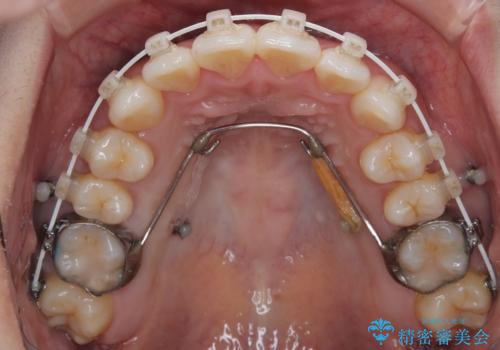

初診時、上下顎ともに歯列の不正が認められ、特に左下の小臼歯が大きく歯列から外れている状態でした。その影響により、下顎の正中が左側へシフトしており、見た目だけでなく噛み合わせにも影響が出ていました。

左下の小臼歯をきれいに歯列内へ並べるためには、まず十分なスペースの確保が必要でした。

そこで本症例では、上顎右側にアンカースクリュー(矯正用インプラント)を埋入し、そこからゴムかけ(顎間ゴム)を行うことで、下顎の正中を右方向へコントロール。

これにより、左下小臼歯がく並ぶためのスペースを確保することができました。

矯正中の見た目にも配慮し、プラスチックブラケット+コーティングワイヤーの目立ちにくい審美装置を採用しました。